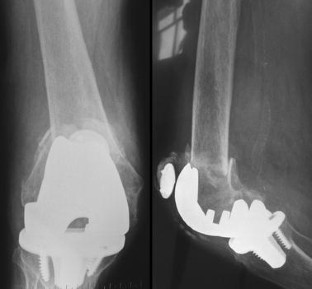

Abb. 8a,b